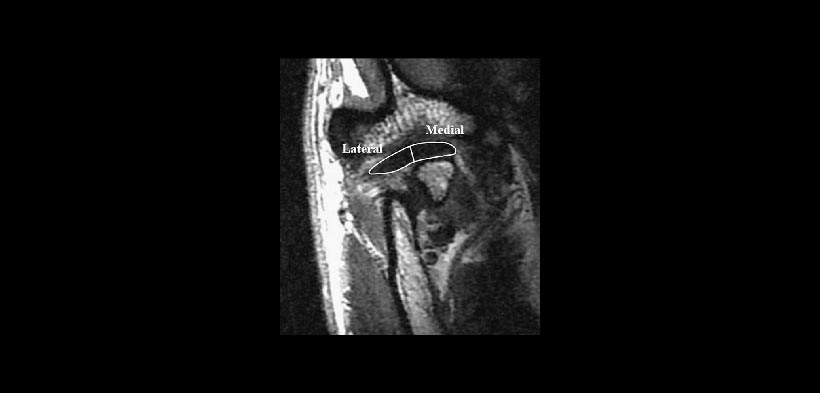

El disco articular solo es posible estudiarlo mediante Resonancia magnética (RM), así podremos localizarla y evaluarla en estática y dinámica mandibular, para poder ofrecer un mejor tratamiento (fg.3 y 4).

Fig. 2. Evaluación del disc articular mediante resonancia magnética (RM). El disco se divide en dos mitades: partes lateral y medial.